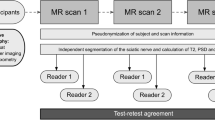

All participants underwent three MR scans on different days, all of which were analyzed by two independent readers (flowchart in Fig. 1). Inclusion criteria were male sex and age between 18 and 35 years. Exclusion criteria were any known diseases of the peripheral nervous system as well as general contraindications for MRI and severe motion artifacts in the MRI examination.

Flowchart of study design. A total number of 27 healthy volunteers underwent MR neurography on 3 separate days, each covering the sciatic nerve in the same anatomical region. Postprocessing and parameter readout was performed by two independent observers. Subsequently, statistical analyses were performed to calculate interreader agreement and test-retest reproducibility